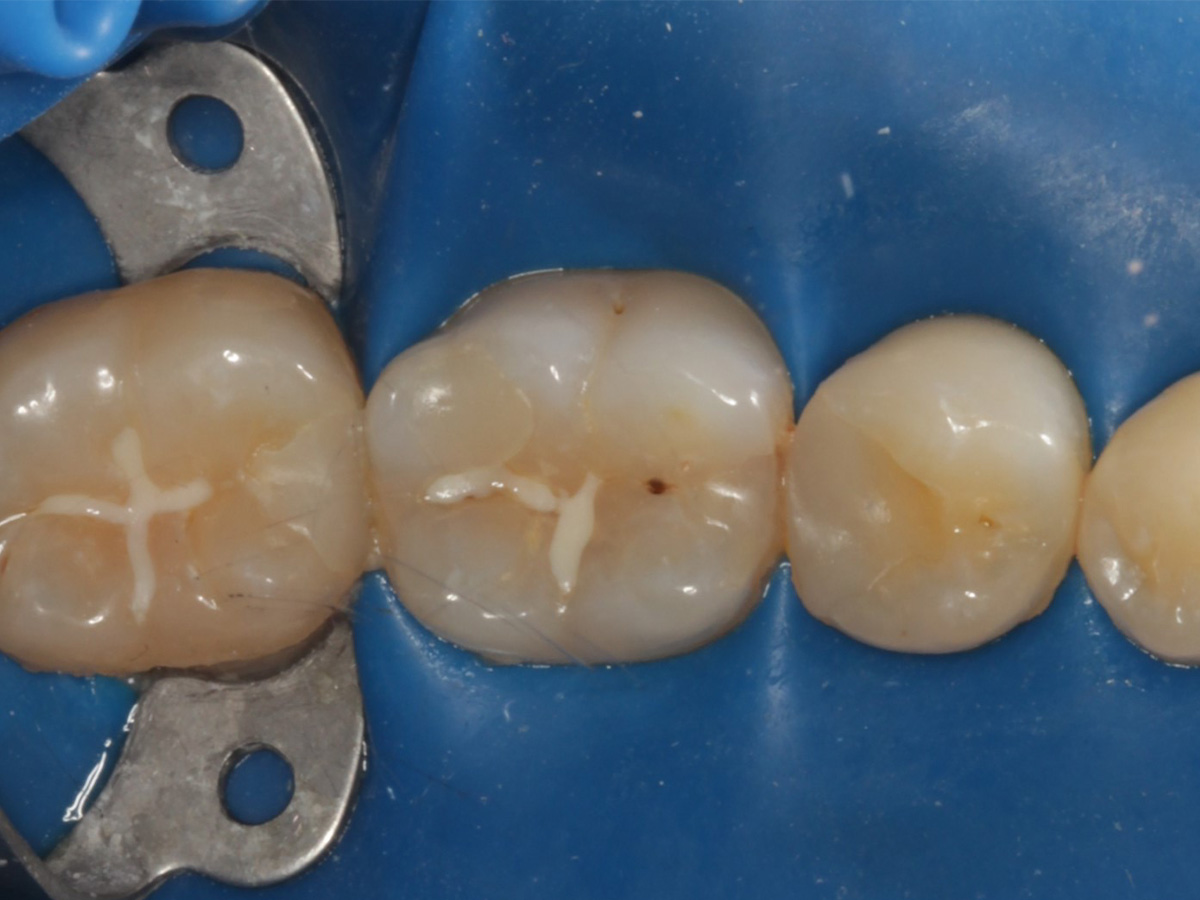

Abbildung 1

Intakte Kaufläche bei Approximalraumkaries an Zahn 36 mesial und distal